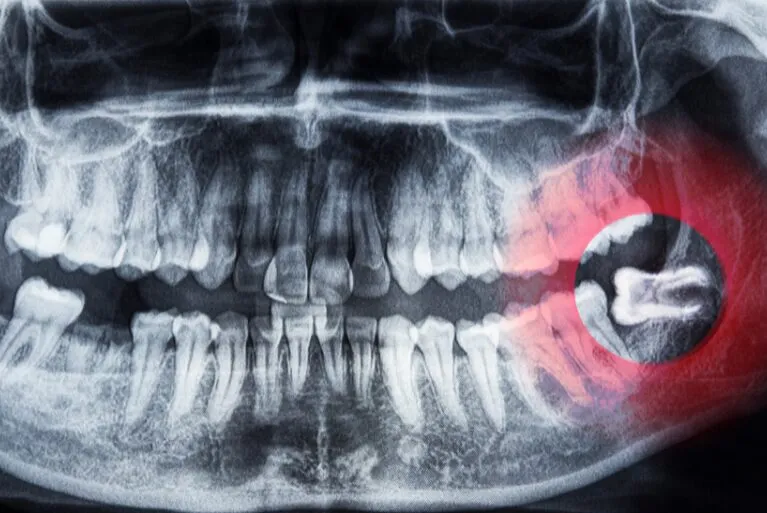

「親知らず」とは、最も奥に位置する歯で、第三大臼歯や智歯とも呼ばれます。親知らずは生えてくる場合と生えてこない場合があり(最初から存在しないこともあります)、一般的には抜歯した方がよいことが多いです。ただし、親知らずを抜かずに残しておいても問題ないケースもあるため、その判断が必要です。

当クリニックでは、完全に埋まっていたり横を向いている親知らずの抜歯も可能です。

まずはCTを含めたレントゲン検査で診断しますので、ご相談ください。

親知らずは生え方により歯磨きが困難な場合があり、むし歯や歯周病のリスクが高まります。最悪の場合、隣接する健康な歯に悪影響を及ぼすため、親知らずの状況によって早期の抜歯が推奨されます。

- 斜めや横向きに生えていたり、一部歯肉に覆われて生えきっていない場合